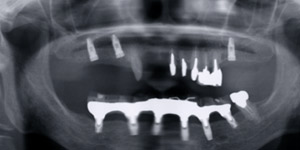

![]() |

上あご両方に3本のインプラントがはいりました。予想通り痛みと腫れはありませんでした。 |